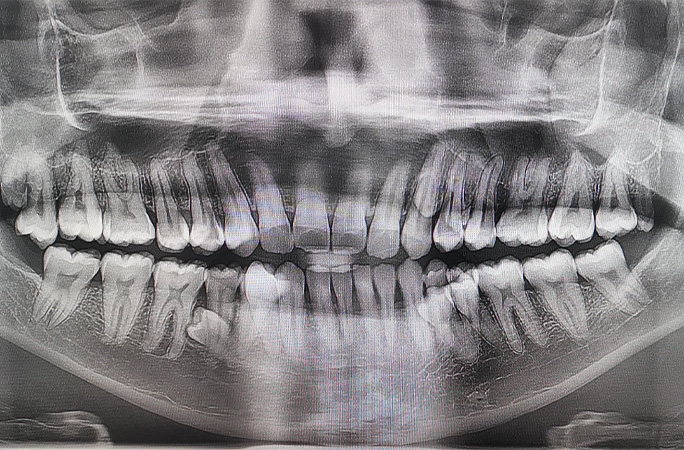

Інженер із Малайзія Пратхаб Муніанді встановив світовий рекорд з найбільшої кількості зубів у роті серед чоловіків. У нього їх 42 — на десять більше, ніж у середньостатистичної людини.

Рекорд офіційно підтвердили у 2023 році після обстежень у двох стоматологів. Цікаво, що в чоловіка є ще два зуби, які поки не прорізалися. А йому, між іншим, вже 33 роки!

Пізніше рентген показав, що у щелепі є ще кілька зубів, які ще не з’явилися. На початку 2023 року стало зрозуміло: загалом їх 42.